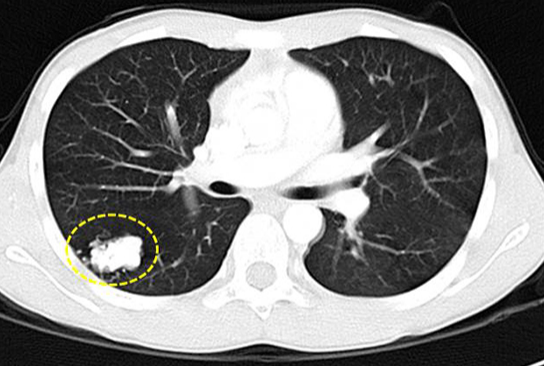

第二,长得比较大,形状比较怪异,密度不均匀的结节,恶性机率高。